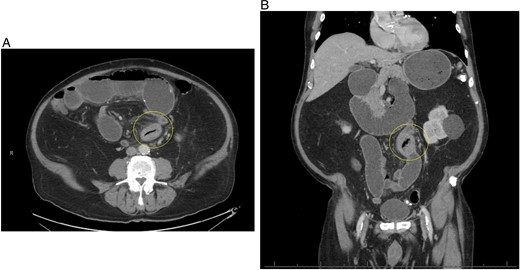

A 77-year-old male with a medical history of hyperlipidemia presented to the emergency department (ED) with diffuse lower abdominal pain. Physical examination revealed mild tenderness in the lower left quadrant. Computed tomography (CT) of the abdomen with oral contrast revealed an abnormally thickened small intestinal loop with possible intussusception causing low-grade partial obstruction (Fig. 1). Due to increasing abdominal pain, the patient underwent diagnostic laparoscopy, and a narrowed segment of the small bowel was found. Intussusception was not seen, the scarred and narrowed segments were resected, and primary stapled anastomosis was performed. The distal collapsed bowel was examined 2 feet from the transition point, and no lesions or masses were observed. The pathology of the resected bowel segment was benign.

(A) Initial CT abdomen (transverse view) revealing what was thought to be intussusception but turns out to be primary enterolith with an air filled core. (B) Initial CT abdomen (coronal view) revealing what was thought to be intussusception but turns out to be primary enterolith with an air filled core.